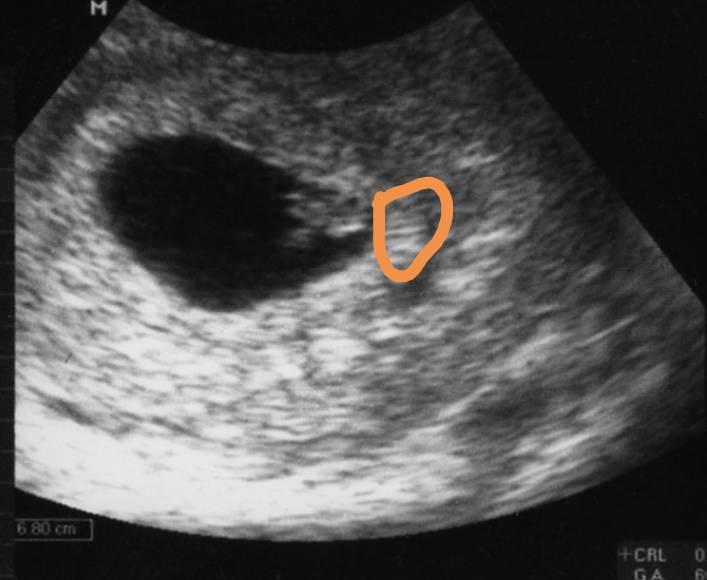

Pokaze wam przykładowo jak to wygląda, moj jest w obrebie tego koloru pomaranczowego jakby sklejony z macica i sie nie odroznia tylko dzieki sercu widac,ze ciaza istnieje, zdjecie z gogle czyjeś , tam jest dziecko prawidłowo

Pokaze wam przykładowo jak to wygląda, moj jest w obrebie tego koloru pomaranczowego jakby sklejony z macica i sie nie odroznia tylko dzieki sercu widac,ze ciaza istnieje, zdjecie z gogle czyjeś , tam jest dziecko prawidłowoZobacz załącznik 882128